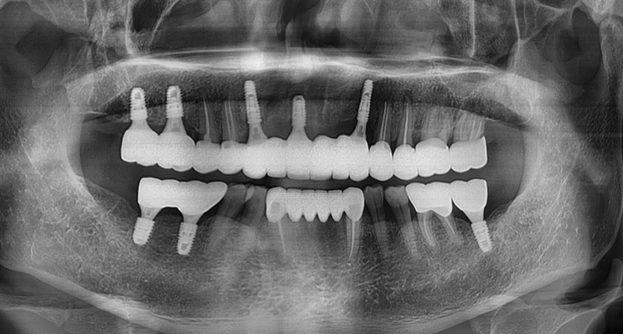

많은 분들이 틀니보다 관리가 편하며

자연 치아와 비슷한 임플란트를 선호합니다.

임플란트는 기능적이나 심미적으로

선호도가 높고 관리가 잘 될 경우

반영구적으로 쓸 수 있기 때문입니다.